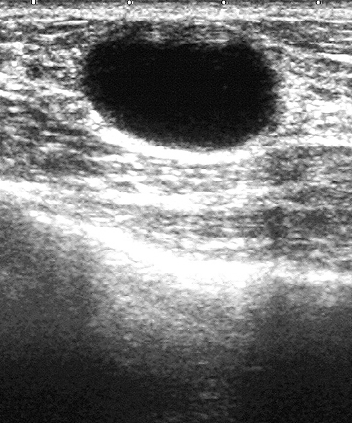

The target dataset was developed from 35 breast ultrasound scans that were segmented by an image-processing expert with extensive experience in breast lesion segmentation (the second author). The images, collected from the Web, are of different dimensions, ranging from to pixels (Figure 3, images resized for sake of illustration). These are the same images used to introduce EFIS originally [1].

Ultrasound images are generally difficult to segment, primarily due to the presence of speckle noise and low level of local contrast. It should be noted that the segmentation of ultrasound actually does require a complete processing chain, (including proper preprocessing and post-processing steps). However, the purpose of using these images was solely to demonstrate that the accuracy of the segmentation can be increased with the application of SC-EFIS.